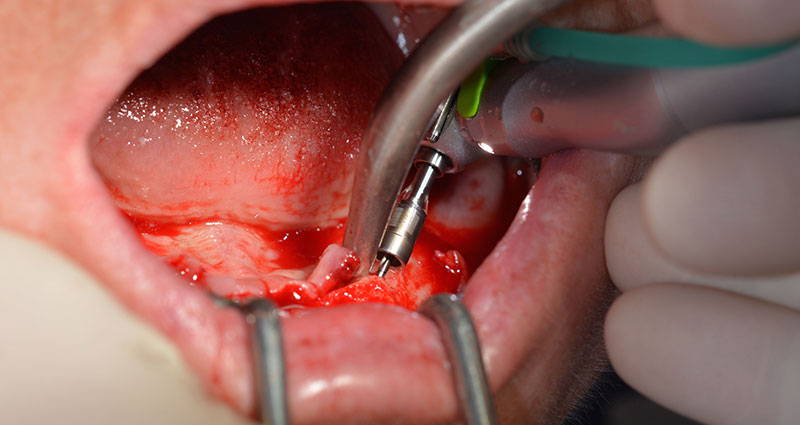

Die nächste programmierte Einstellung ist bereits die Implantateinbringung. Die Implantate werden in unserem Hause standardmäßig mit einer Kraft von 32Ncm inseriert (Abb. 12 und 13).

Die absolute Voraussetzung für die Sofortversorgung ist die hohe Primärstabilität. Um diese zu erfüllen, wurde in diesem Fall auf ein Gewindeschneiden verzichtet. Die hier verwendete Antriebseinheit Implantmed von W&H besitzt hierfür einen eigenen Modus, der ebenfalls direkt anwählbar und für viele Indikationen unverzichtbar ist. Die letzten Umdrehungen bei der Implantateinbringung überschritten den Wert von 32Ncm und wurden manuell durchgeführt. Hierfür empfiehlt es sich, die Selbstschneidefunktion der Implantate auszunutzen und das Implantat mehrmals vorwärts und rückwärts zu drehen. So gelangt das Implantat schrittweise näher bis zur endgültigen Position, ohne zu starken Druck auf den Knochen auszuüben (Abb. 14).